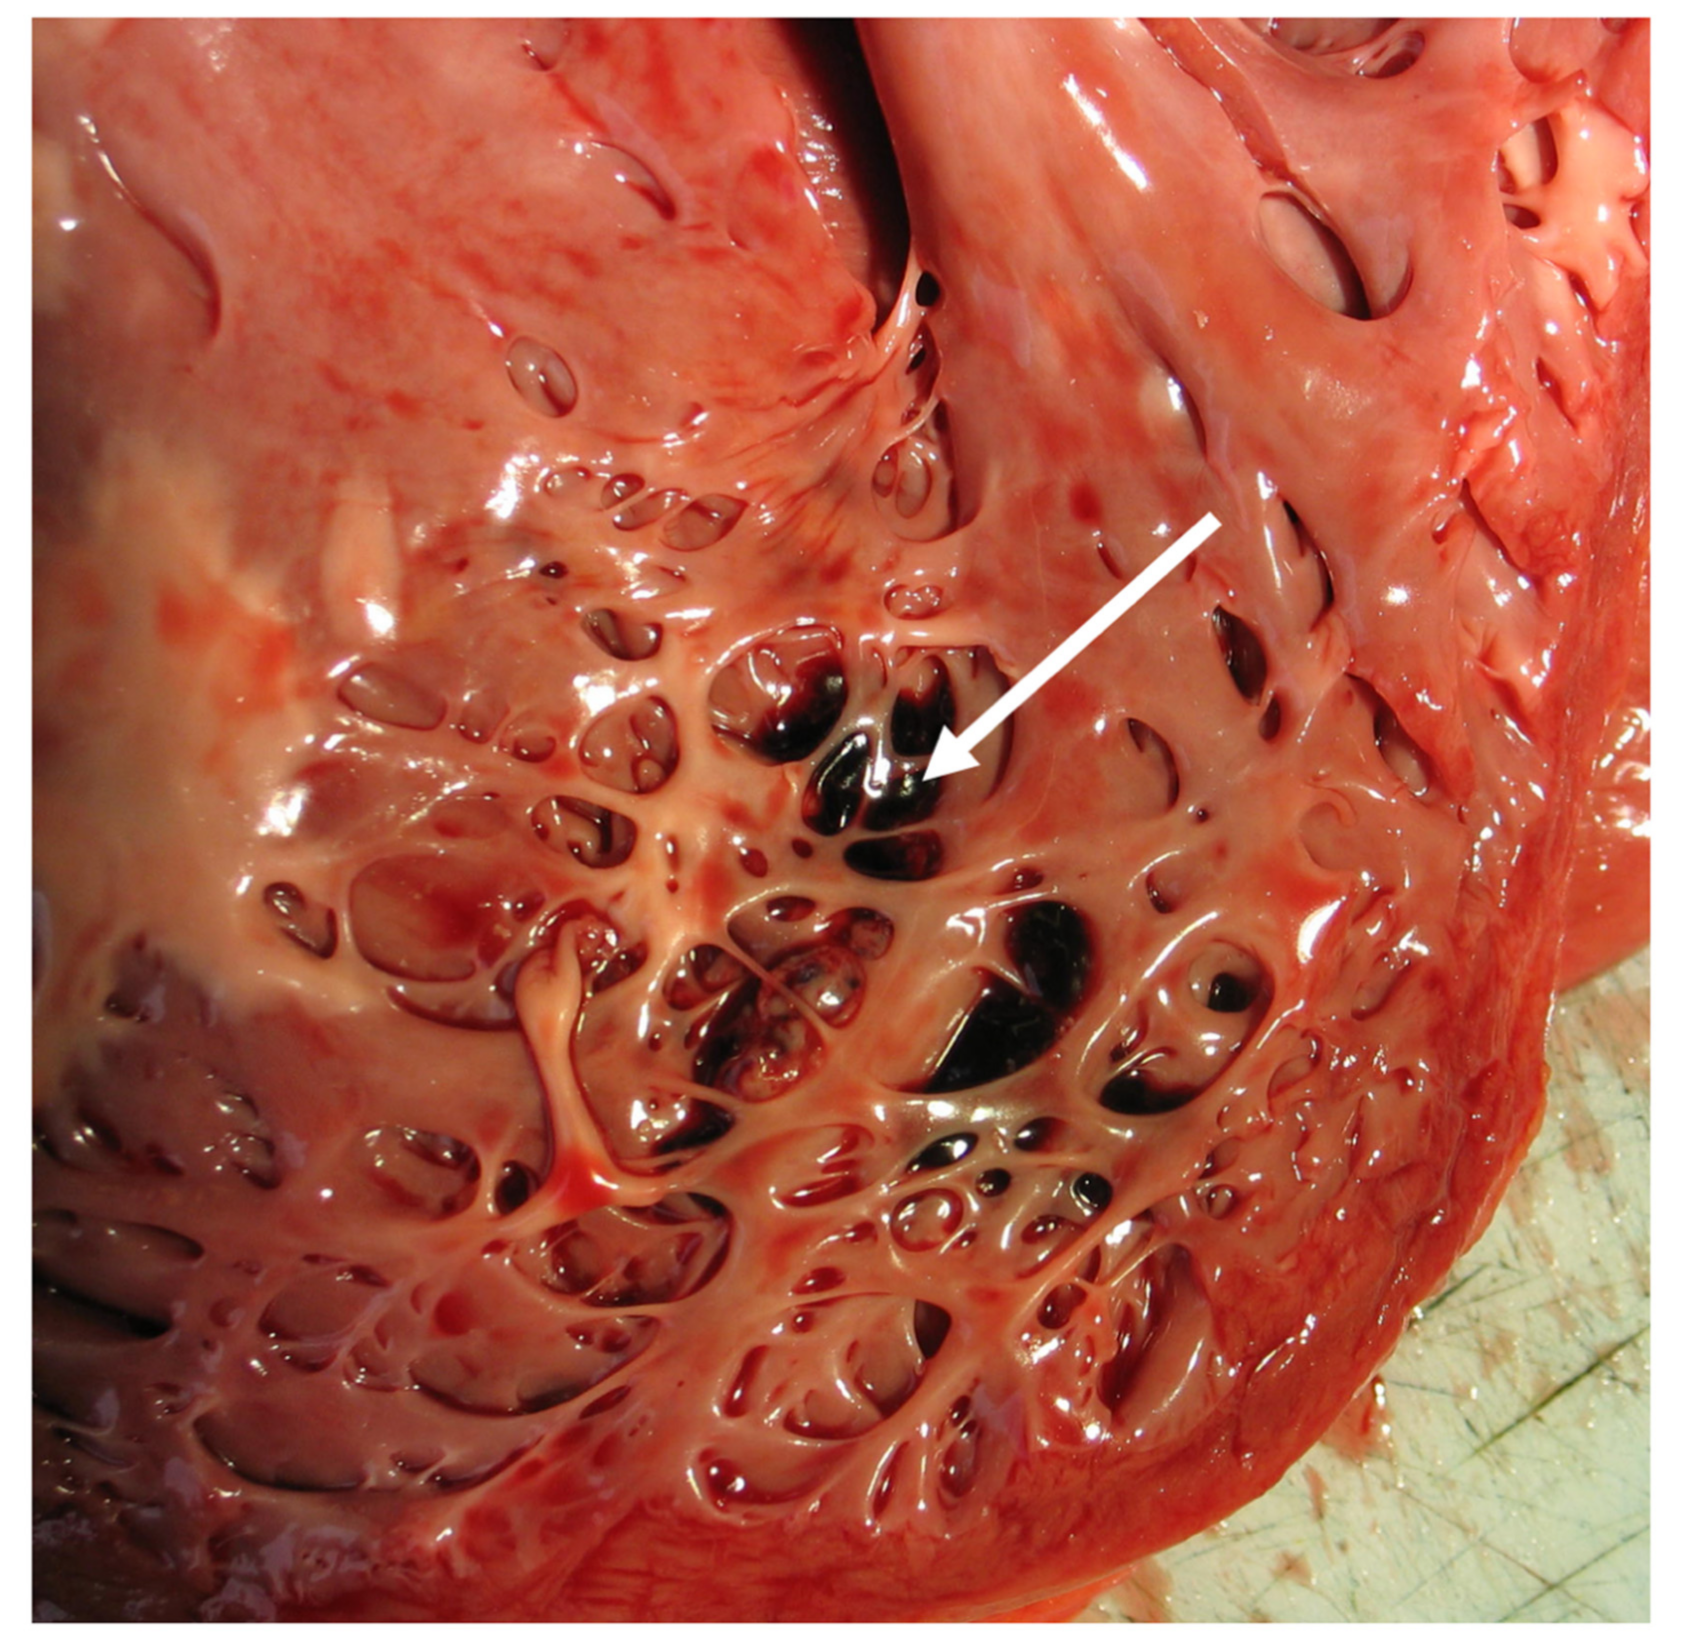

10. Pathology

- Burke, A.; Mont, E.; Kutys, R.; Virmani, R. Left ventricular noncompaction: A pathological study of 14 cases. Hum. Pathol. 2005, 36, 403–411. [Google Scholar] [CrossRef] [PubMed]